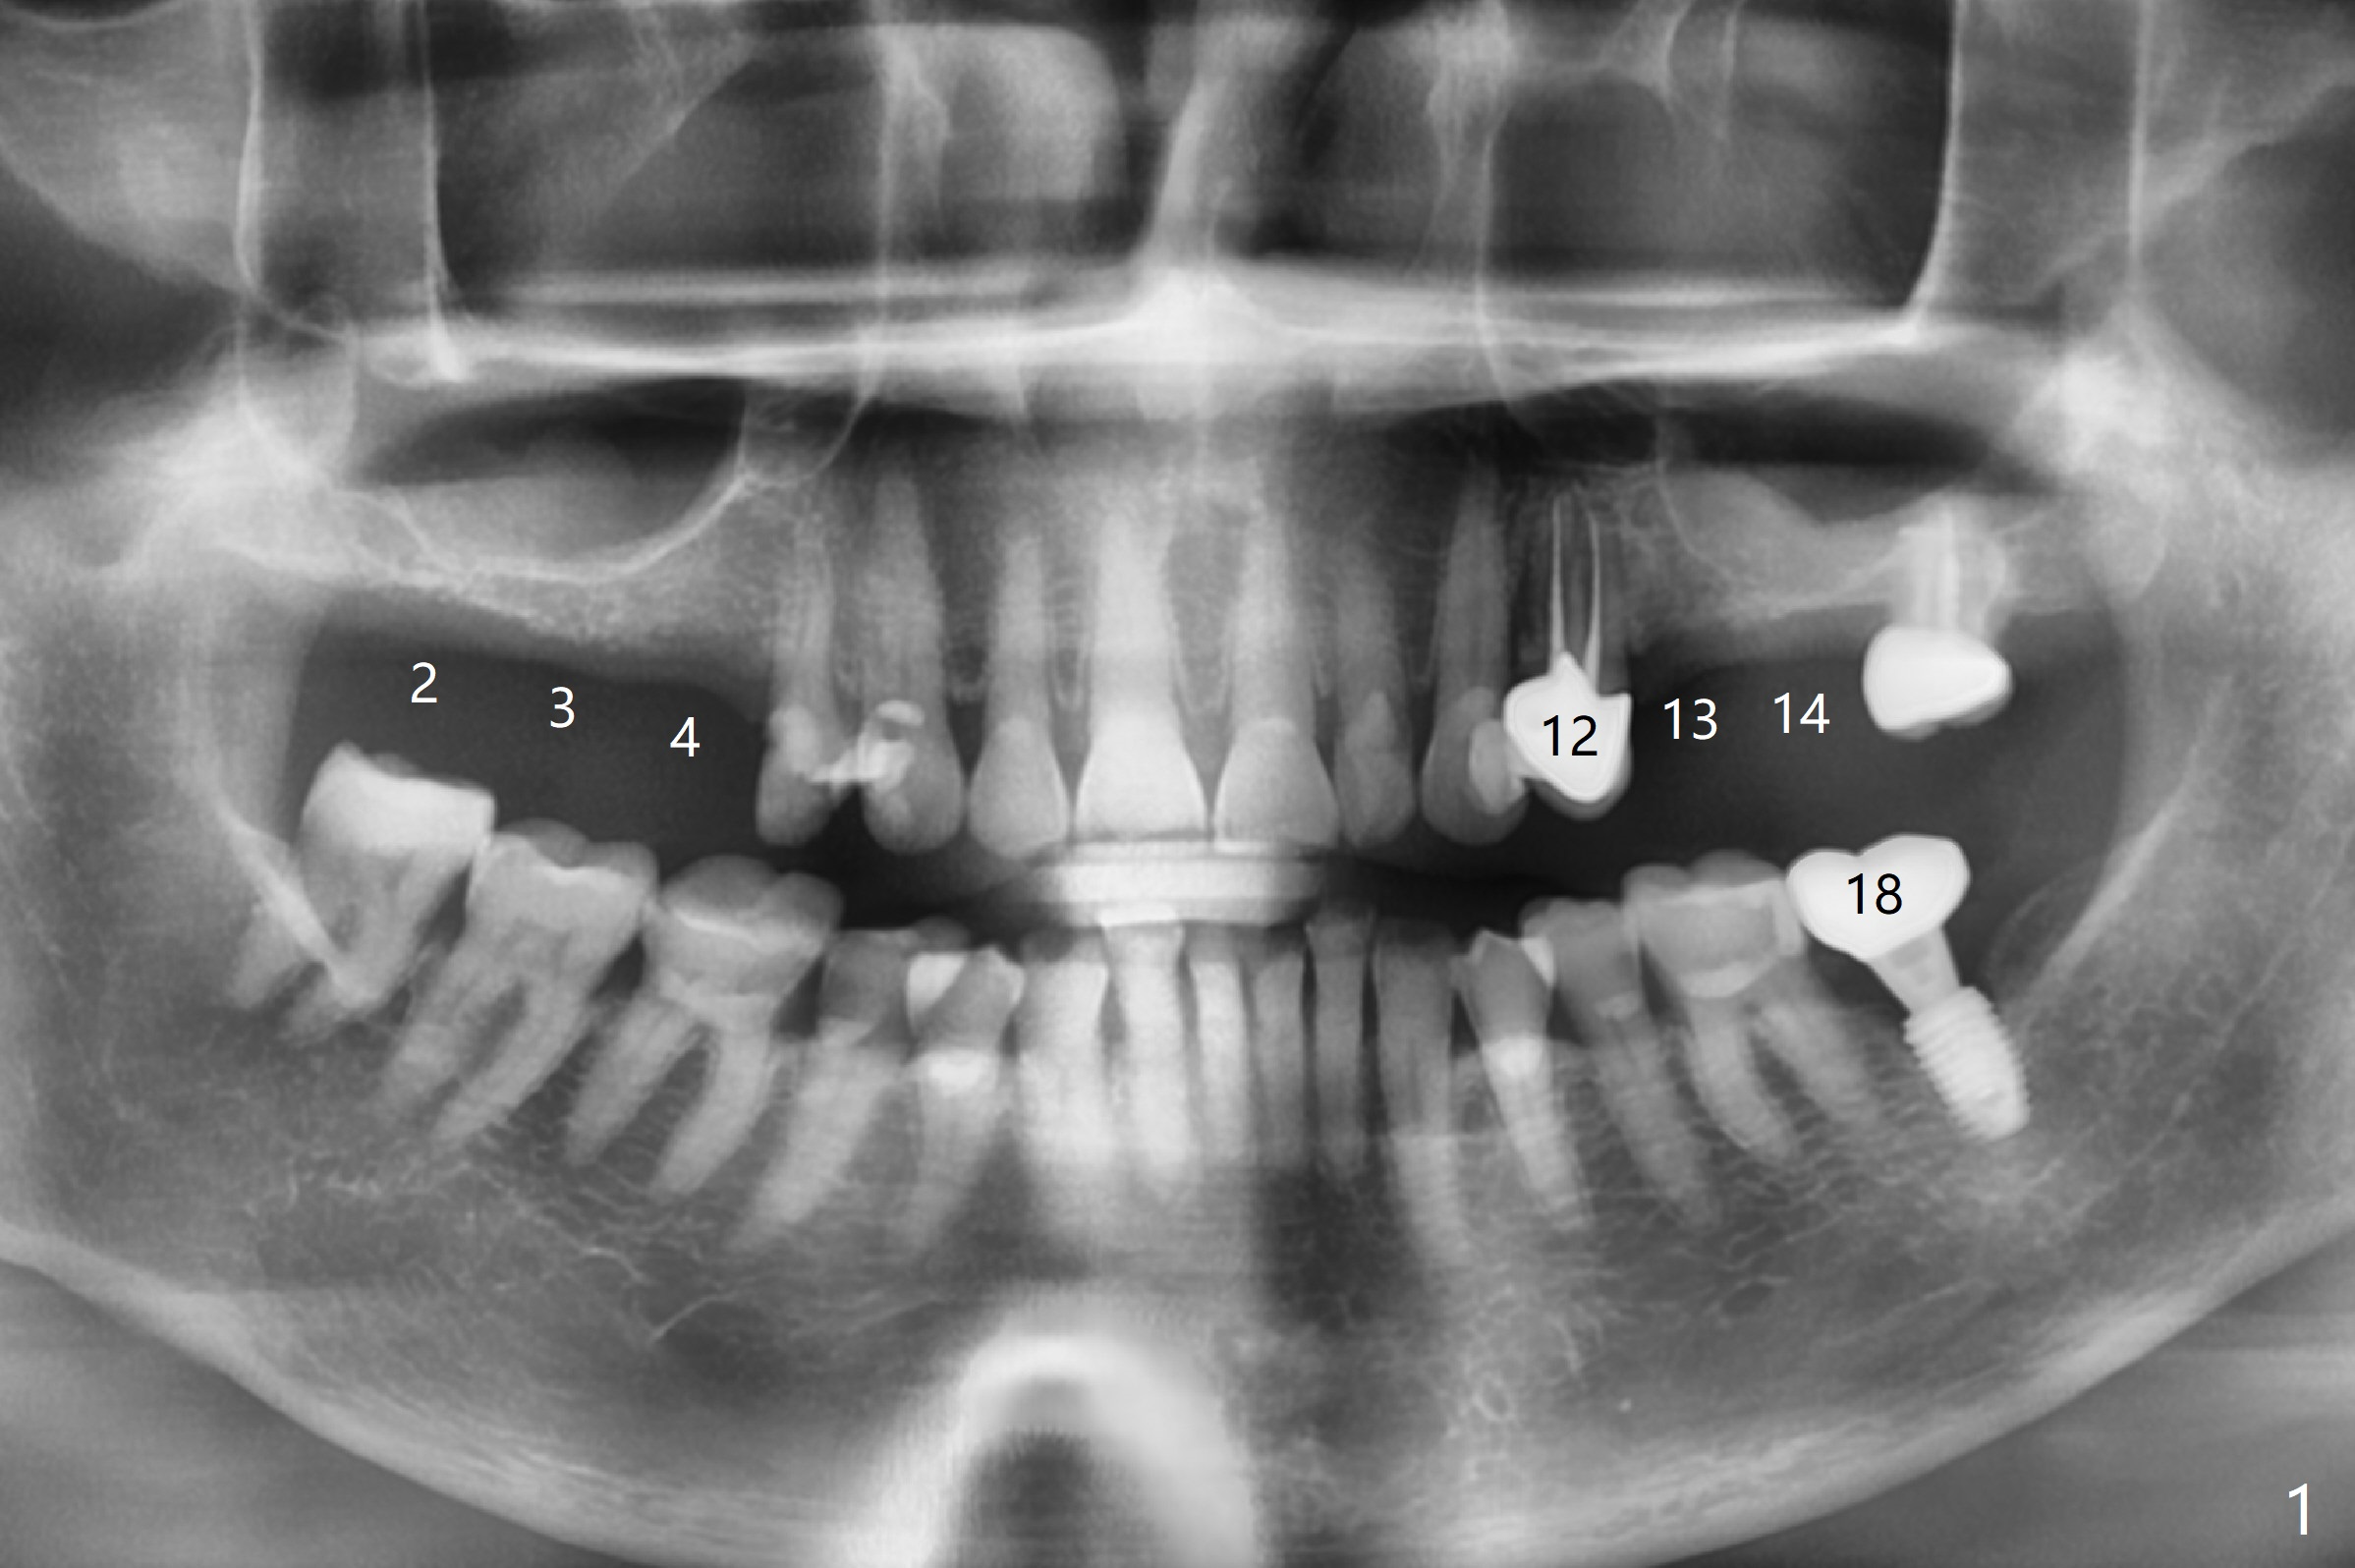

A 63-year-old woman wants to change upper RPD (for #2-4, 13 and 14) to implants because of denture-associated candidiasis. She is afraid of osteoporosis, although the implant at #18 is doing fine almost 3 months post cementation (Fig.1). One way to restore the upper right quadrant is to place 3 short implants (7.3 or 8.5 mm) with guide with simultaneous internal or external sinus lift (Fig.2-4). The tooth #12 appears to have root fracture with periradicular radiolucency (Fig.5); an immediate implant will be placed. While a short implant will be placed at #13, no implant will be placed at #14 because of 1 mm bone (Fig.6). A cantilever FPD will be fabricated in the upper left quadrant. The thick left sinus membrane is a problem as related to a lift?